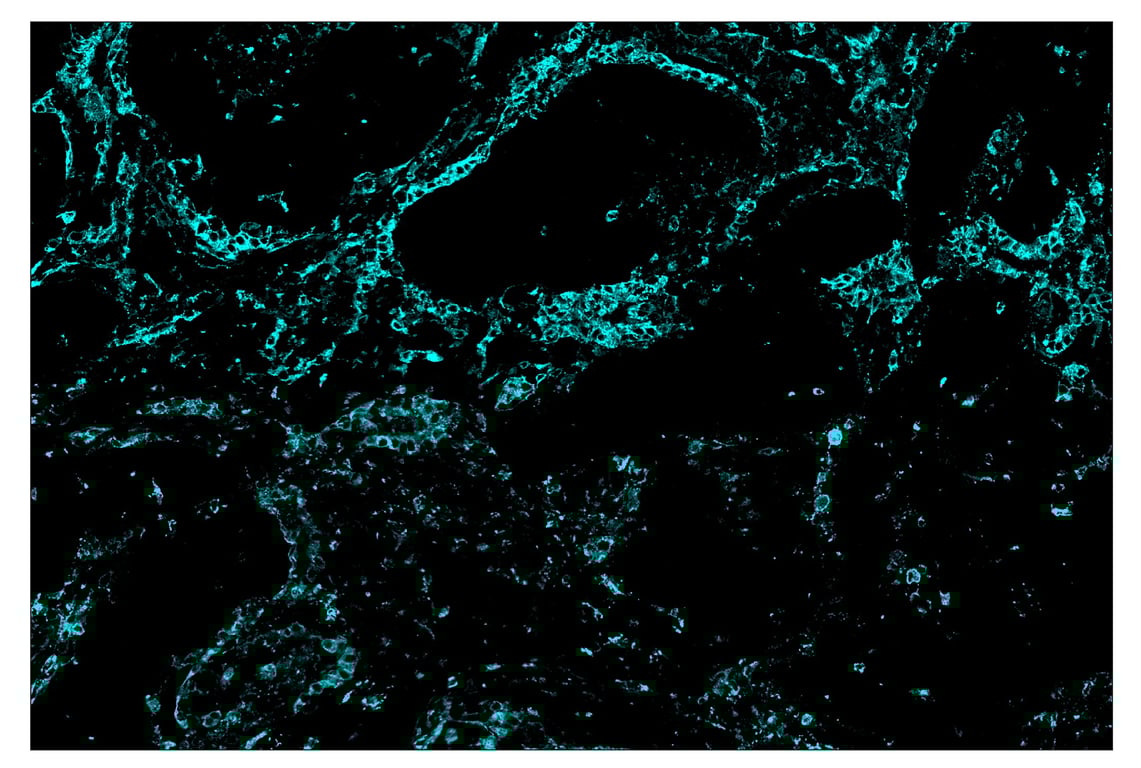

SignalStar™ immunohistochemical analysis of paraffin-embedded human squamous cell lung carcinoma using HLA-DRA (E9R2Q) & CO-0023-750 SignalStar™ Oligo-Antibody Pair #58446 (cyan). All fluorophores have been assigned a pseudocolor, as indicated. Staining was performed on the BOND RX by Leica Biosystems.

Immunohistochemistry Image 5: HLA-DRA (E9R2Q) & CO-0023-647 SignalStar<sup>™</sup> Oligo-Antibody Pair